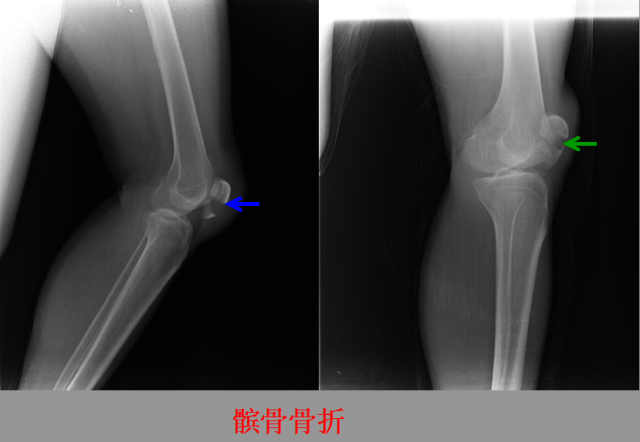

骨折篇

01

定义:骨折{Fracture}是指骨的完整性和连续性的折裂或粉碎。包括创伤性骨折、疲劳性骨折和病例理性骨折。 临床上以创伤性骨折*常见。